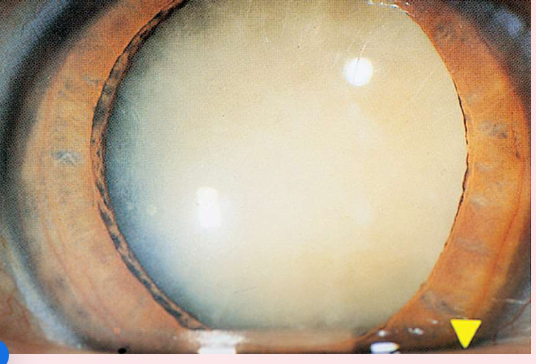

Nuclear cataracts

appear gray when seen with a flashlight; they appear as a black spot against the red reflex

Peripheral cataracts

look like gray spokes that point inward when seen with a flashlight; they look like black spokes that point inward against the red reflex when seen through an ophthalmoscope.